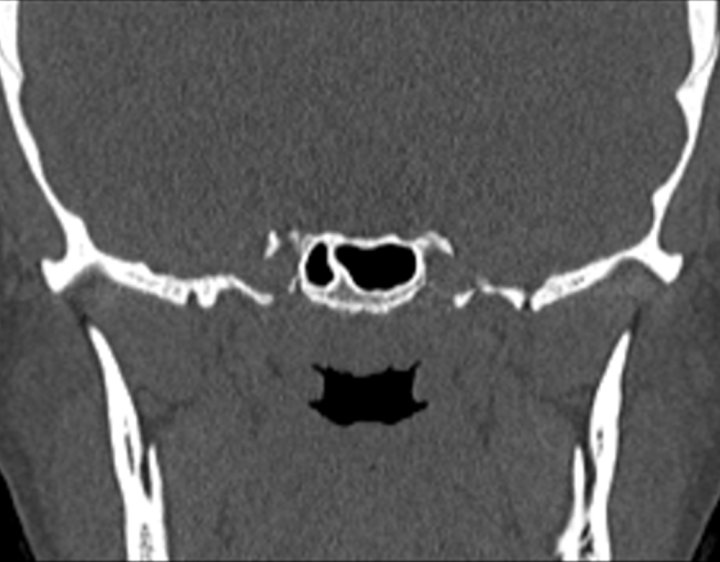

Click any image for labels.